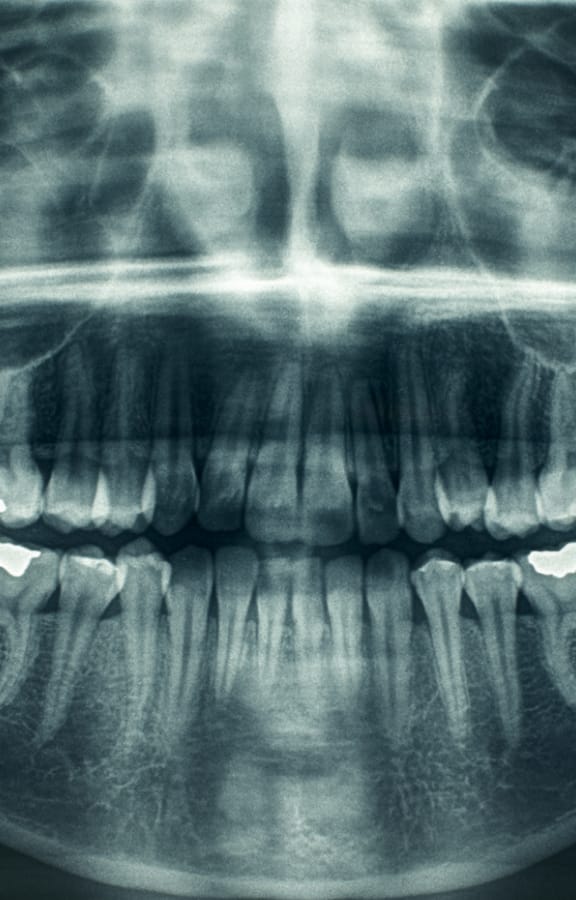

Bone grafting is commonly performed by an oral and maxillofacial surgeon to replace or augment bone in areas of tooth loss. Bone grafting to the jaws and facial structures may be necessary in a wide variety of scenarios. The most common bone grafts are facial skeleton and jaw procedures. Other common procedures include tooth extraction site graft, bone graft reconstruction and for a sinus lift. Shrinkage of bone often occurs when a tooth is lost due to trauma, severe caries, or periodontal disease. Additionally, bone loss may have already occurred due to infection or pathology around a tooth. There are many artificial biocompatible bone substitutes available; however, the best material for a bone graft is your own bone, which most likely will come from your chin, the back part of your lower jaw or your hip bone. The hip is considered to be a better source because the hip bone has a lot of marrow, which contains bone-forming cells. There are also synthetic materials that can be used for bone grafting. Most bone grafts use a person's own bone, possibly in combination with other materials.

To place the removed bone in the recipient site, little holes are drilled in the existing bone to cause bleeding. This is done because blood provides cells that help the bone heal. The block of bone that was removed will be anchored in place with titanium screws. A mixture of the patient's bone marrow and some other bone-graft material will then be placed around the edges of bone block. Finally, a membrane is placed over the area and the incision closed.

The bone graft will take about 6 to 12 months to heal before dental implants can be placed. At that time, the titanium screws used to anchor the bone block in place will be removed before the implant is placed.